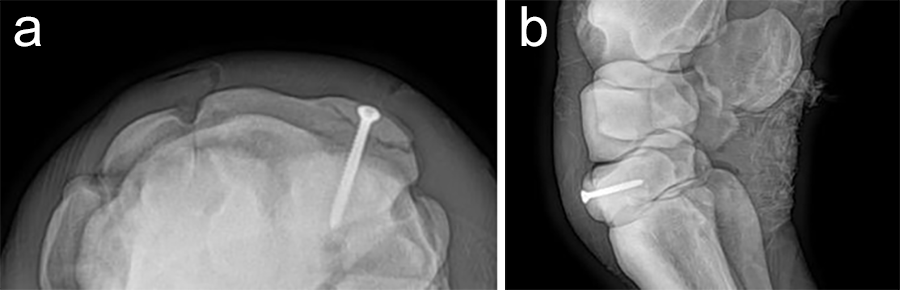

An articular fracture of the lateral wing of the distal phalanx was diagnosed at the track in this 3-year-old Standardbred racehorse, which was referred for surgery. Internal fixation was planned with a 5.5 mm cortex screw in lag fashion to restore and maintain articular congruency by fracture reduction and interfragmentary compression. Drill trajectory was planned with computed tomographic (CT) guidance with the horse awake and standing. Grids of barium paste dots were placed at proposed entry and projected exit sites. Once the ideal dot was selected from each grid the horse was anesthetized and the hoof prepared for surgery. The veterinary Screw Targeting Clamp (STC) was affixed to the hoof at the ideal dot in the entry and exit grids. Drilling, countersinking, measuring, tapping, and screw placement were achieved through the STC. The CT guidance and the STC allowed placement of the screw between the articular surface and vascular canal containing the terminal arterial arch, and in an orientation that resulted in accurate reduction instead of translation of the fracture fragment and parent bone.